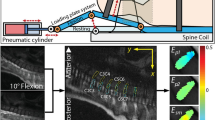

For each sample, the details of the laminated AF can be seen on FA maps due to its relatively high anisotropy. These match well with the structure of the lamellae as determined by 2D histology and by 2D scanning microscope image (Fig. 1A–C). A 3D reconstruction of one sample is shown in Fig. 1D. The differences in the observed diffusion anisotropy exemplify the structural variation throughout the non-uniform lamellae width.

A portion of the outer AF and its structure. Two-dimensional high-resolution histological images of the AF (axial section) using light microscopy (A, B): The different orientations of the fiber tracts in each lamella are clearly seen in (A), whereas (B) (Masson Trichrome stain) presents the complex structure of the AF. The 2D scanning microscope image yielded a consistent arrangement (C). DTI generated 3D FA data where distinct concentric lamellae rings are seen (as in the histological sections), since they are associated with anisotropic water diffusion (D). The scheme (E) shows lamellae layers with alternating orientation fibers surrounding the nucleus pulposus (center).

Fiber tracking qualitative analysis

A detailed 3D image of the AF could be presented using fiber tracking (Fig. 2A, B). The laminated structure of the AF reveals fiber tracts that cross each other in alternating directions and that vary considerably in thickness, spatial density, and inclination angle throughout each sample and between the samples (see Movie S1 for a video clip of the 3D structure in the supplementary).

Structure of the AF. (A) A dense fiber tracts network typical of the 3D disc reconstruction via DTI followed by fiber tracking. For visualization purpose only 1 in 30 fiber tracts is displayed. (B) An enlargement of the yellow square showing parallel layers of the lamellae displaying the expected structure of crossing fiber tracts in alternating directions composing the AF. Large variations are apparent among the fiber tracts thickness, length density, and orientation. The divison into the three anatomical regions can be seen on the T2 weighted image (C). Normalized diffusion parameters analyzed by anatomical region with standard deviation (D). FA increases significantly between the inner and both the middle (p < 0.05) and outer (p < 0.001) regions (Kruskal–Wallis test). MD, λ1, and λ2 do not show significant variations between the three regions. λ3 is the only diffusion value showing a significant difference between the inner and outer region (p < 0.01). The mean morphological parameters analyzed by region (n = 8) with standard deviation (E). Owing to the large variations between samples, we normalized the parameters to the inner region. The inner region differs significantly from the middle and outer regions regarding the inclination angle, the number of fiber tracts, and in the tracts' length (Kruskal–Wallis test). The inclination angle shows a decreasing trend from the inner to the outer aspect of the AF, and a significant difference between both the inner and middle (p = 0.001) and the outer (p < 0.05) regions. The number of fiber tracts differs significantly between the inner and both the middle (p = 0.001) and the outer (p = 0.005) regions. A clear trend can also be seen as the mean fiber tract length increases towards the outer portion of the AF, and a significant difference is seen between the inner and both the middle (p < 0.005) and outer (p < 0.001) regions of the AF.